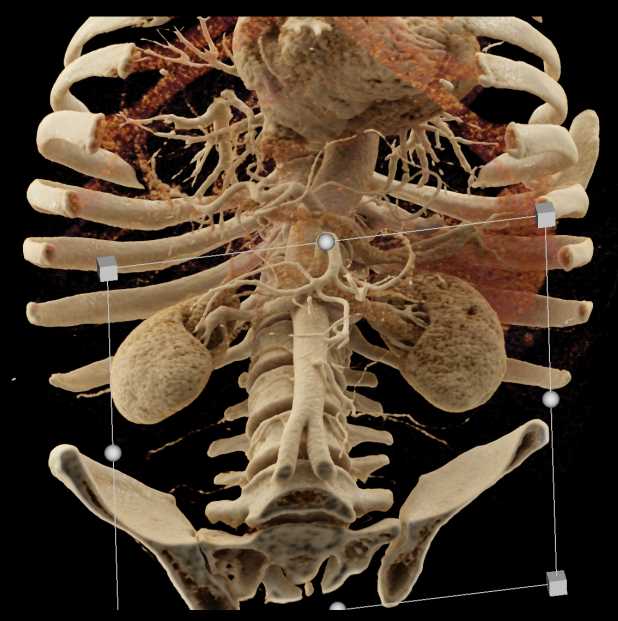

Small Bowel Obstruction (SBO) with Thickened Small Bowel Folds